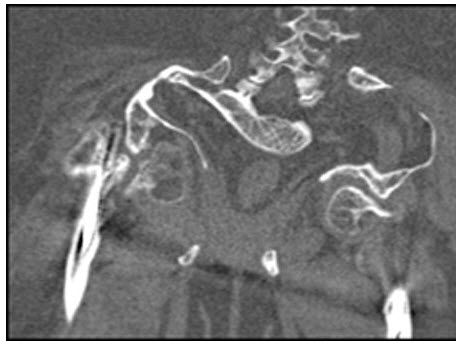

65、多项选择题

女,6个月,CT扫描如图所示,下列说法正确的是()

A.双侧肾盂积水

B.双侧肾门朝向前内方

C.双肾下极融合

D.考虑为异位肾

E.考虑为马蹄肾